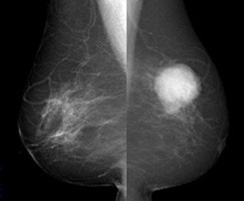

Æý˼XÀþ»£±Æ¡Ê¥Þ¥ó¥â¥°¥é¥Õ¥£¡Ë¤Ï¡¢¼ê¤Ç¿¨¤Ã¤Æ¤â¤ï¤«¤é¤Ê¤¤¤è¤¦¤Ê¤´¤¯Áá´ü¤ÎÆý¤¬¤ó¤ò¡¢Çò¤¤±Æ¡Ê

¼ðáî±Æ¡Ë¤äº½¤Î¤è¤¦¤ÊºÙ¤«¤ÊÀг¥²½¤È¤·¤ÆÈ¯¸«¤Ç¤¤ë¸¡ºº¤Ç¤¹¡£¸¡ºº¤Ç¤ÏÆý˼¤ò°µÇ÷ÈĤȤ¤¤¦ÈĤǤϤµ¤ß»£±Æ¤·¤Þ¤¹¡£Äˤߤòȼ¤¦¤³¤È¤¬¤¢¤ê¤Þ¤¹¤¬¡¢ÆýÁ£¤òÇö¤¯¿¤Ð¤·¤Æ½Å¤Ê¤ê¤ò¸º¤é¤¹¤³¤È¤Ç¡¢¾®¤µ¤ÊÉÂÊѤâÁ¯ÌÀ¤Ë¼Ì¤·½Ð¤¹¤³¤È¤¬¤Ç¤¤Þ¤¹¡£É¬Íפ˱þ¤¸¤Æ¥È¥â¥·¥ó¥»¥·¥¹¡Ê3D¥Þ¥ó¥â¥°¥é¥Õ¥£¡Ë¤Ë¤è¤ëÀºÌ©¸¡ºº¤â¹Ô¤Ã¤Æ¤¤¤Þ¤¹¡£